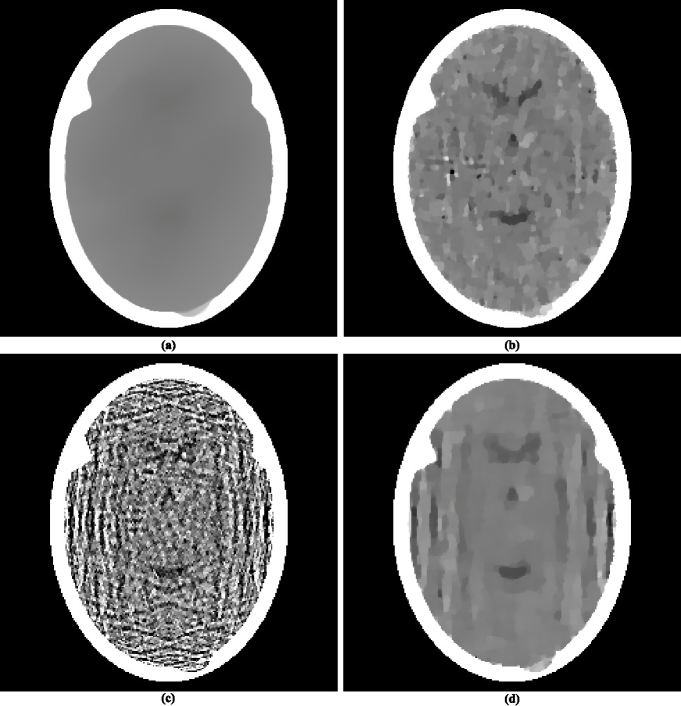

The reconstruction in figure 2(a) produced by ASD-POCS definitely “looks better” than a reconstruction in HERM08a (31), which was obtained using superiorization from similar data. Since, as discussed in the last paragraph of the previous subsection, the ASD-POCS algorithm in SIDK08a (42) can be obtained as a special case of superiorization, it must be that some of the choices made in the details of the implementations are responsible for the visual differences. An analysis of the implementational details adopted by the two approaches revealed several differences. After removing these differences, the superiorization approach produced the image in figure 2(b), which is very similar to the reconstruction produced by ASD-POCS. We now list the implementational choices that were made for superiorization to make its performance match that of the reported implementation of ASD-POCS.

One implementational difference is in the stopping-rule of the iterative algorithm; that is, the choice of in determining the output . Since the data are noisy, the phantom itself does not match the data exactly. In previously reported implementations of superiorization it was assumed that the iterative process should terminate when an image is obtained that is approximately as constraints-compatible as the phantom; in the case of the phantom and the projections data on which we report here the value of for the phantom is approximately 0.91, which is larger than its value (0.33) for the reconstruction produced by ASD-POCS. The output is shown in figure 3(a). This is a wonderfully smooth reconstruction, its value is only 771. However this smoothness comes at a price: we loose not only the ability to detect the large tumor, but we cannot even see anatomic features (such as the ventricular cavities) inside the brain. So it appears that, in order to see medically-relevant features in the brain, over-fitting (in the sense of producing a reconstruction from noisy data that is more constraints-compatible than the phantom) is desirable.

In the implementations that produced previously reported reconstructions by superiorization, the number in the Superiorized Version of Algorithm was always chosen to be 1. It is possible that this is the wrong choice, making only this change to what lead to the reconstruction in figure 2(b) results in the reconstruction shown in figure 3(b). That image appears similar to the image in figure 2(b), but it has a higher value, namely 832, which is still very slightly lower than that of the ASD-POCS reconstruction. The choice was based on the desire to maintain consistency with what has been practiced using ASD-POCS, see page 4790 of SIDK08a (42). It appears that in the context of our paper the additional computing cost due to choosing to be 20 rather than 1 is not really justified. (We note that if is selected using subgradients as discussed in the paragraph following (7) and thus is not guaranteed to be a nonascending vector for the function, then the choice of 20 rather than 1 for results in a considerable improvement. However, an even greater improvement is achieved even with by selecting as recommended in this paper.)

Another important difference between the ASD-POCS implementation and the previous implementations of the superiorization approach is the size of the pixels in the reconstructions. For the ASD-POCS reconstruction this was selected to be 0.376 mm by 0.376 mm. In previously reported reconstructions by superiorization it was assumed that the edge of a pixel should be the same as the distance between the parallel lines along which the data are collected; that is, 0.752 mm for our problem . This assumption proved to be false. -minimization takes care of undesirable artifacts that may otherwise arise due to the smaller pixels and this leads to a visual improvement. A superiorizing reconstruction with the larger pixels, using and , is shown in figure 3(c). (We note that the use of smaller pixels during iterative x-ray CT reconstructions was also suggested inZBIJ04a (59). However, that approach is quite different from what is presented here: its final result uses larger pixels whose values are obtained by averaging assemblies of values provided by the iterative process to the smaller pixels. There is no such downsampling in our approach, our final result is presented using the smaller pixels. Its smoothness is due to reduction of TV by the superiorization approach rather than to averaging pixel values in a denser digitization.)

Combining the use of the larger pixels with and results in the reconstruction shown in figure 3(d). This reconstruction, for which the superiorization options were selected according to what was done inHERM08a (31), is visually inferior to those shown in our figure 2. The reconstructions displayed in figure 3 also illustrate another important point, namely that even though the mathematical results discussed in this paper are valid for a large range of choices of the parameters in the superiorization algorithms, for medical efficacy of the reconstructions attention has to be paid to these choices since they can have a drastic effect on the quality of the reconstruction.

It has been mentioned in Subsection II.2 that except for the presence of in (3), which enforces nonnegativity of the components, is identical to the algorithm used and illustrated in HERM08a (31). It is known that CT reconstruction of the brain from many views does not suffer from ignoring the fact that the components of the , which represent linear attenuation coefficients, should be nonnegative; as is illustrated in figure 1(b). This remains so when reconstructing from a few views using the method and data that we have been discussing: if we do everything in exactly the same way as was done to obtain the reconstruction with value 826 that is shown in our figure 2(b) but remove from (3), then we obtain a reconstruction in figure 4(a) whose value is 829.

Another variation that deserves discussion, because it has been suggested in the literature PENF10a (22), is one that does not come about by making choices for the general approach of the Superiorized Version of Algorithm but rather by changing the nature of the approach. The variation in question is not applicable in general, but can be applied to the special case when the algorithm to be superiorized is the defined by (3). It was suggested as an improvement to the approach presented above with the choice . The idea was based on recognizing the block-iterative nature of the algorithmic operator in (3) and intermingling the perturbation steps of lines (vii)-(xvii) of the Superiorized Version of Algorithm with the projection steps of (3). It was reported in PENF10a (22) that doing this is advantageous to using the Superiorized Version of Algorithm . However, when we applied the variation of the Superiorized Version of Algorithm that is proposed in PENF10a (22) to the problem that we have been using in this section, we ended up with the reconstruction in figure 4(b) whose value is 920. This is not as good as what was obtained using the version of the algorithm that produced the reconstruction in figure 2(b). We conclude that the variation suggested by PENF10a (22), which does not fit into the theory of our paper, does not have an advantage over what we are proposing here, at least for the problem that we have been discussing in this section. We conjecture that the improvement reported in PENF10a (22) is due to selecting using subgradients as discussed in the paragraph following (7) and, as discussed earlier, such an improvement is not obtained if is selected by the more appropriate method recommended in this paper.